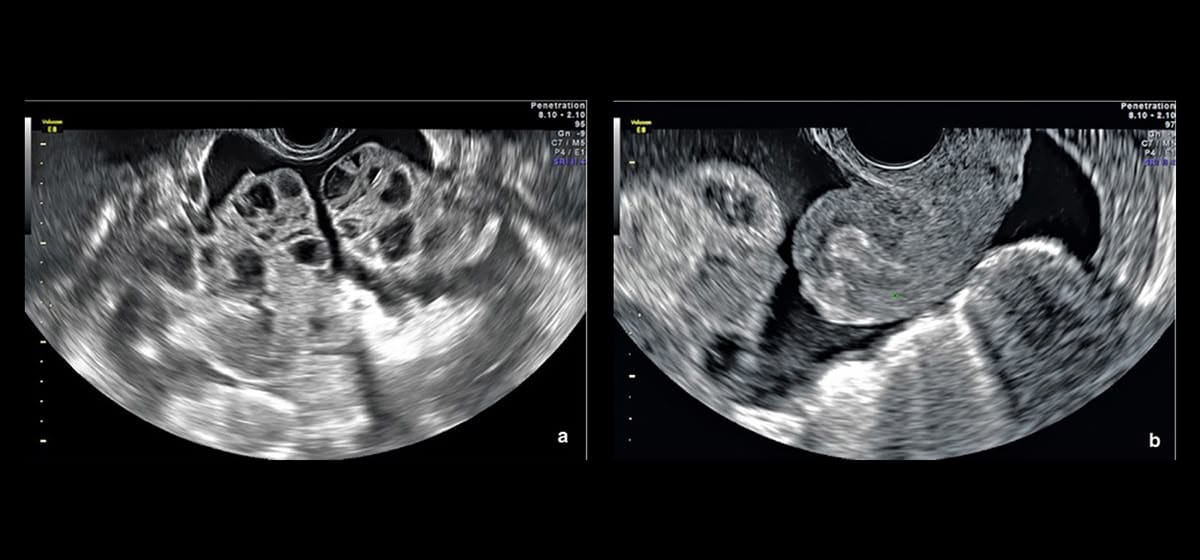

2. Theo dõi chặt chẽ trong quá trình điều trị

Theo dõi chặt chẽ bằng các phương pháp hình ảnh như siêu âm và xét nghiệm máu giúp đánh giá mức độ phản ứng của buồng trứng với thuốc. Việc theo dõi này cho phép bác sĩ can thiệp kịp thời, điều chỉnh liều lượng, hoặc thậm chí ngưng điều trị nếu có dấu hiệu của quá kích buồng trứng.

Sau khi điều trị quá kích buồng trứng, việc theo dõi sức khỏe định kỳ là rất quan trọng. Các bác sĩ có thể khuyến nghị siêu âm định kỳ hoặc các xét nghiệm máu để kiểm tra tình trạng buồng trứng và mức độ hoạt động hormone. Việc này giúp phát hiện sớm các dấu hiệu tái phát hoặc các vấn đề khác liên quan đến sức khỏe sinh sản.